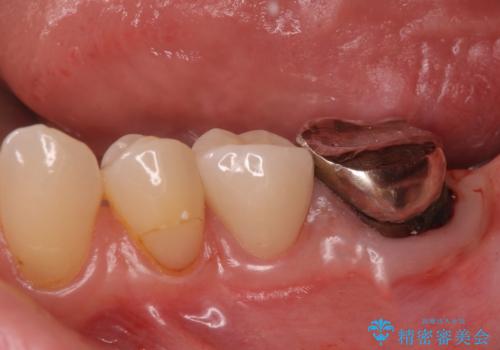

レントゲン上で根尖病巣が見られた場合

中の土台を外して根管治療を行わなくてはなりません。

また根尖病巣がなくて土台を変えたい(メタルから白の土台)場合

土台を外すと根管内が細菌感染する恐れがあるために根管治療をやり直す必要があります。